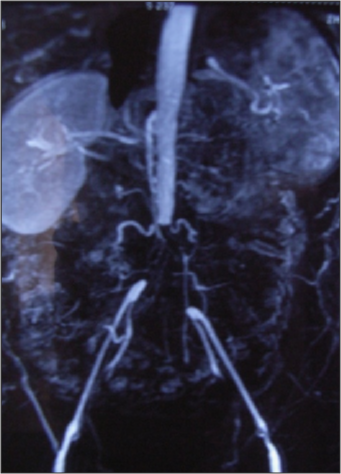

女性、80岁,诊断为主-髂动脉闭塞

通过预置导管溶栓成功开通闭塞段,术后血流恢复,治疗效果满意。